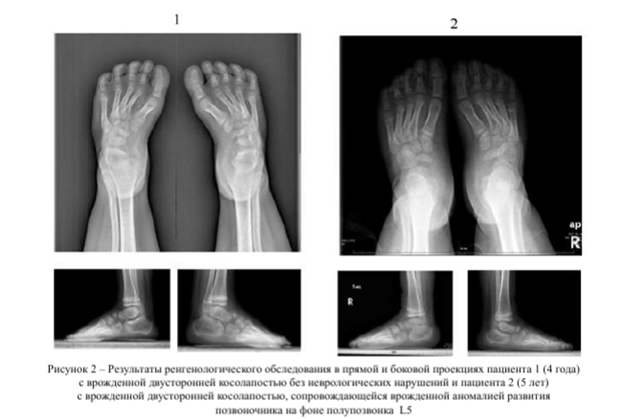

Для объективизации этих изменений БА дополнительно проводили исследование методом стимуляционной ЭМГ и с помощью регистрации МО при транскраниальной магнитной стимуляции. Анализ результатов нейрофизиологического исследования проводили с учетом клинико-лучевой диагностики. По данным рентгенологического обследования у пациентов обеих групп деформация стопы характеризовалась фиксированной инверсией среднего отдела стопы (подошвенным сгибанием, приведением, супинацией) и варус- ным положением пяточной кости в сочетании с эквинусным компонентом. У пациентов II группы деформация костно-суставных структур стопы была более выраженной (рис. 2).